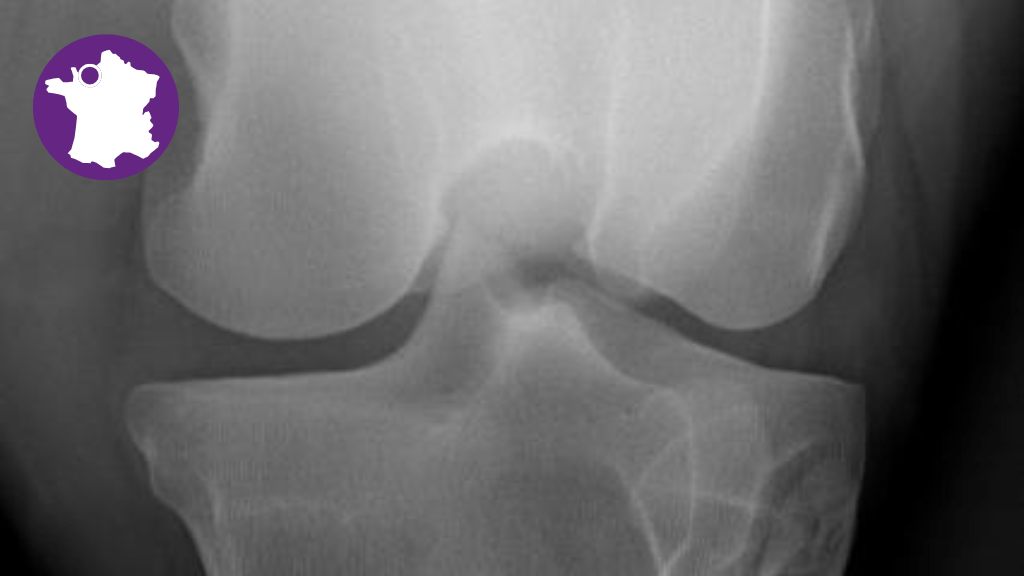

Bannière visuelle de présentation de la formation